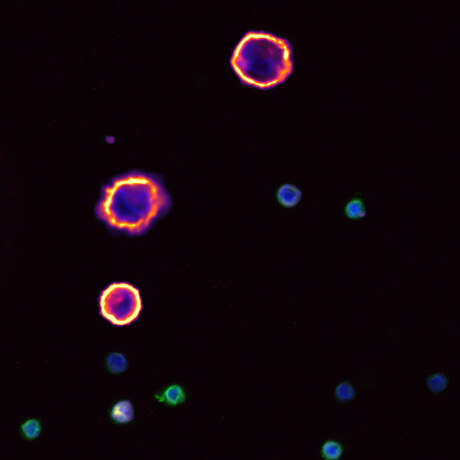

An alternative to solid tissue biopsies is the liquid biopsy, which is performed using blood and other bodily fluids. The test detects circulating tumour DNA (ctDNA) and circulating tumour cells (CTCs).

Becker and Lock are collaborating to develop liquid biopsy approaches to monitor a patient’s cancer over time. Clinicians can then use the information about the cancer to adapt the treatment plan. In their research, Becker and Lock are answering questions like: How can we easily tell CTCs apart from other cells? And how can we get as much information as possible from each CTC?